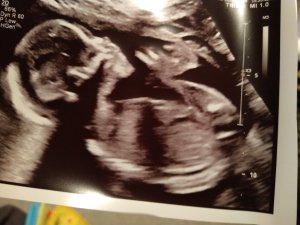

Idag har jag mått oförskämt bra måste jag erkänna. Om det inte varit för foglossningen och förvärkarna hade jag knappt trott att jag var gravid 😅 Sovit riktigt bra, pigg i huvudet och sugen på att hitta på massor av saker även om man är väldigt begränsad just nu både pga kroppen och pandemin. Men det är inte illa att må såhär dagen innan beräknad förlossning! Hoppas att det håller i sig till det är dags 😊

Vi hoppas på en bebis under nästa vecka, men det återstår att se 😅 Men jag har börjat skapa en hel del planer för att få tiden att gå för nästa vecka men vi får väl se om jag får chansen att utföra dem eller inte.